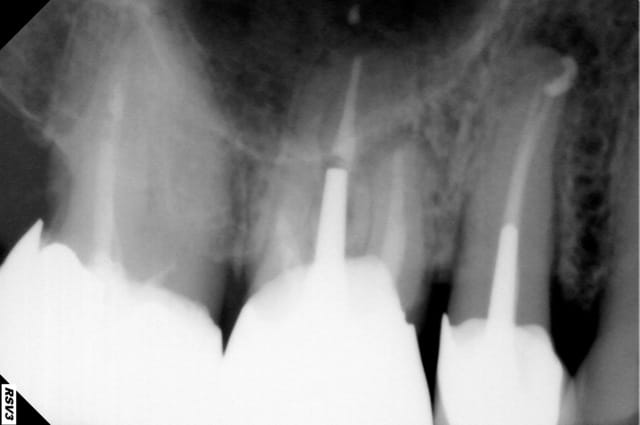

J'ai reçu un Patient de 85 ans qui vient faire un bilan avant traitement au bisphospho pour cancer de la prostate.

J'ai trouvé une lésion apicale niveau de la 15, sensible à la palpation et à la percussion

La couronne date de 2009, le traitement est plus que correct mais je n'en ai as trace dans le dossier